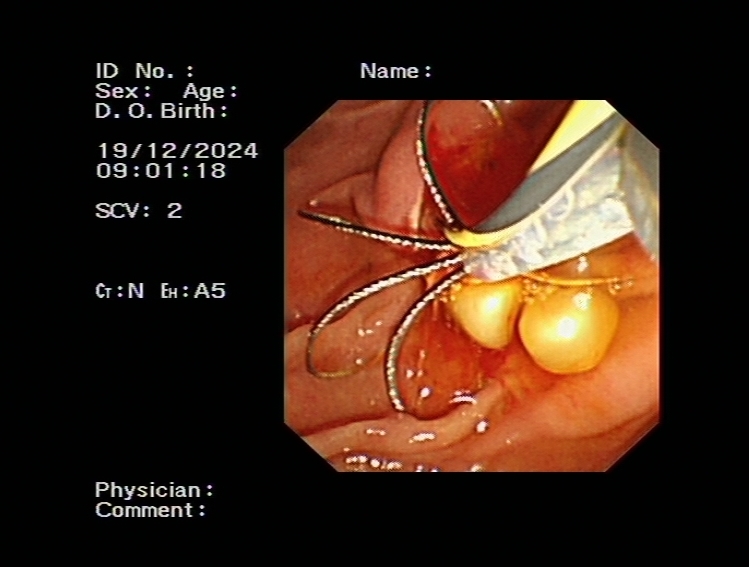

、ERCP(內(nèi)鏡逆行胰膽管造影術(shù))

ERCP(內(nèi)鏡逆行胰膽管造影術(shù))是膽胰疾病精準(zhǔn)內(nèi)鏡診療技術(shù),具有不開腹、風(fēng)險(xiǎn)小、創(chuàng)傷小、恢復(fù)快、住院時(shí)間大大縮短的優(yōu)點(diǎn),尤其是對年齡大、體弱多病的患者尤為適宜。ERCP主要運(yùn)用于膽總管結(jié)石的取出,以及在經(jīng)口膽道子鏡的輔助下完成肝內(nèi)膽管結(jié)石的取出。

bc72d6558d394d8ea787e762f054a7c5.Jpeg74bcac877ae44a9da8e58dab53d178ee.Jpeg75e90c629e6545de9ee764d5e15bc91e.JpegERCP取出膽總管結(jié)石